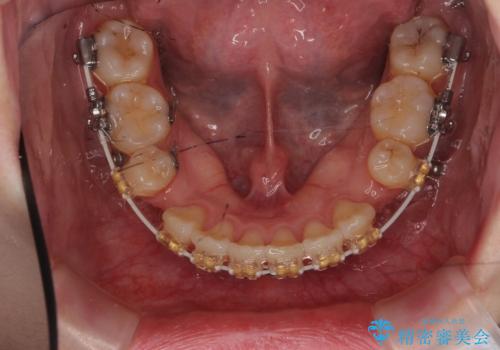

下顎の大臼歯が前に倒れこんでいたため、矯正用ミニスクリューで後ろに起こしています。